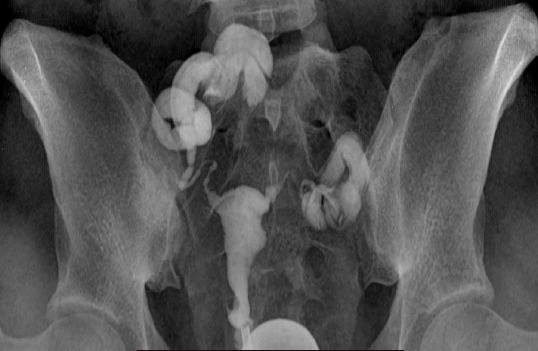

Results: The mean age was 34.65 (6.18) years, and the age group 30 - 39 years had the highest frequency of infertility. The mean duration of infertility was 4.93 (3.88) years, and secondary infertility (77.8%) was higher than primary infertility (22.2%). Tubal pathology was the most common (36.1%), followed by uterine pathology (30.0%), where the tubal blockage was 82.5% and hydrosalpinx was 17.5%. There were 57 (54.8%) and 47 (45.2%) patients with single and bilateral tubal blockage, respectively. Hydrosalpinx was observed in four (20%), nine (45%), and seven patients (35%) with a right, left and bilateral distribution, respectively. Univariate regression analysis showed older women with tubal pathology were 2.01 times more likely to be infertile than the younger patients (95% CI: 1.042 - 4.100, p = 0.005), and patients with longer duration of infertility were 1.1 more likely to be infertile than patients with shorter infertility duration (95% CI: 0.995 - 1.187, p = 0.010). Of the microbes, 33.9% and 22.2% were isolated in the high vaginal and endocervical swabs of participants with tubal pathologies.

Abstract Image